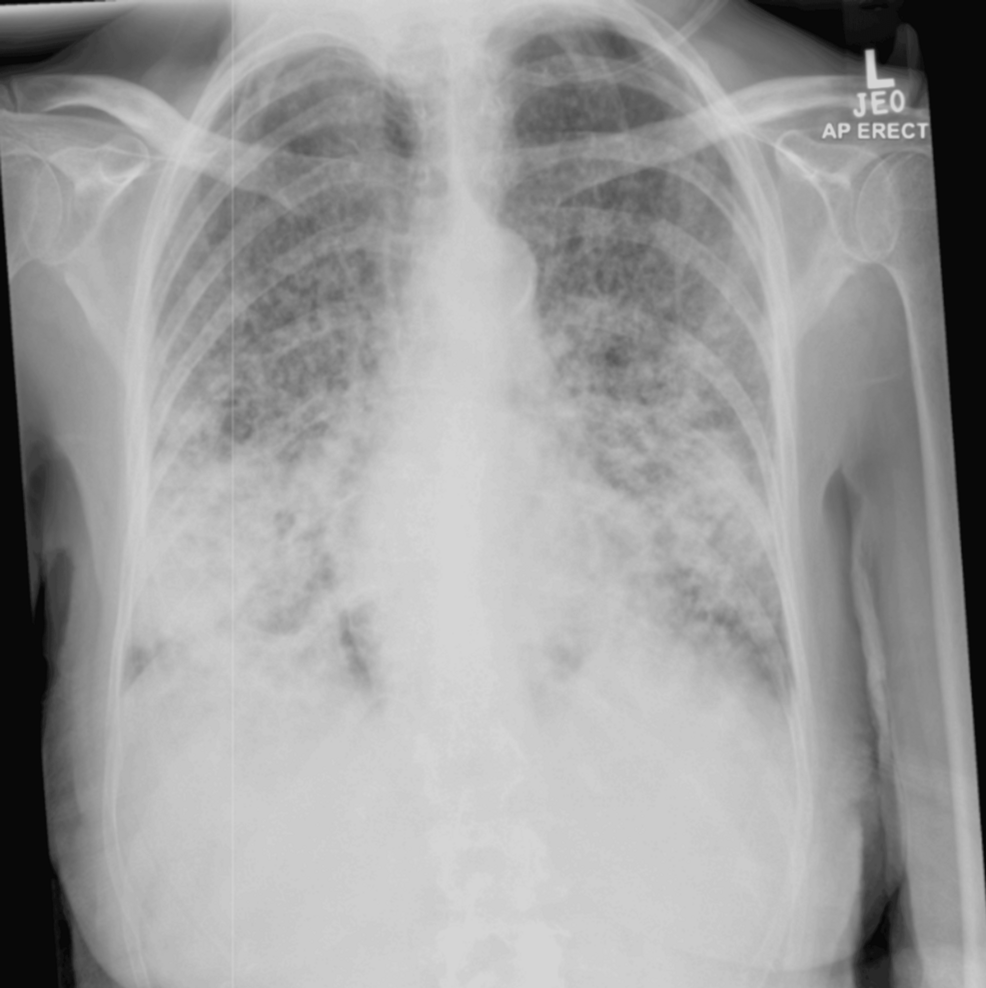

影像学检查:胸部X线提示双肺纤维化改变(图1);胸部CT显示双肺多发小叶中心性结节,以支气管血管周围、裂周和胸膜下区域为主,下叶为著(图2)。

图1 首次就诊时的胸部X线检查